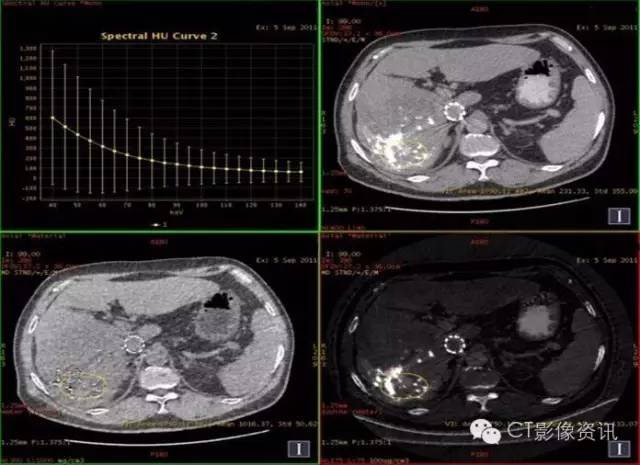

病史资料 男性,56岁,肝癌栓塞术后复查。

扫描参数 模式:GSI-22 375mA@0.7sec/rot@DC40mm@SFOV Body Large 螺距:0.984:1 平扫+增强扫描

平扫:碘9.03,水1018.90

结论:此例平扫、增强多期碘基物质定量无显著差异。栓塞治疗效果较好。

临床优势 肝癌栓塞后,因碘油和术后炎性反应的影响,短期内难以评估手术效果。通过能谱成像GSI分析,比较增强后碘含量与平扫时碘含量(有时可用水含量)的变化及变化趋势,来判断肝癌病灶是否还有强化,评估栓塞治疗的疗效和预后,并可指导临床进一步治疗。